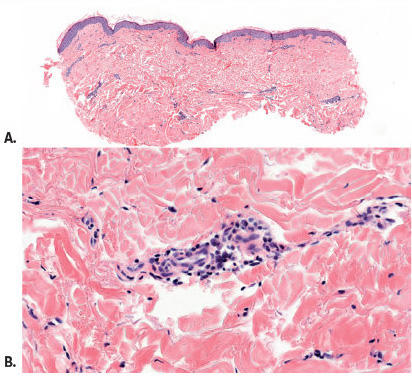

Dermatologie